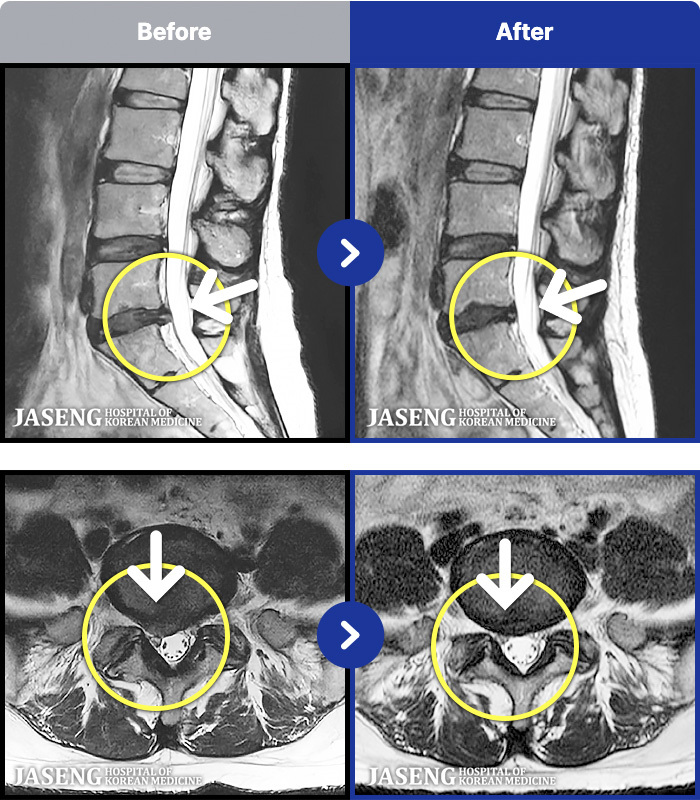

1,287 MRI ũ ʸ Ȯϼ.

[ϻ] 24.07.25~25.08.01

ȯںп Ǹ ǿ ԿǾ, ο ġ ۿ Ƿ ġḦ Ͻñ ٶϴ.